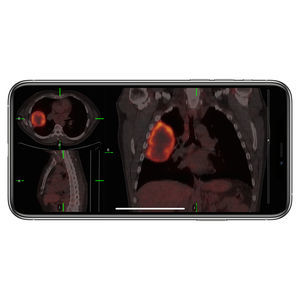

- Aplicación para iOS de importación

Aplicaciones para iOS de importación

... Las aplicaciones MobiPACS™, que trabajan conjuntamente con los sistemas PACS (Picture Archiving and Communication Systems), permiten a los médicos recuperar, visualizar y comparar cualquier tipo de imagen médica. Una gama de aplicaciones ...

... Incluso puede ver fusiones de imágenes y películas MIP en 3D con sombreado de profundidad de sus exploraciones PET y SPECT. Importación de escaneos en MIMcloud VueMe trabaja con MIMcloud para darle un lugar para gestionar sus imágenes ...